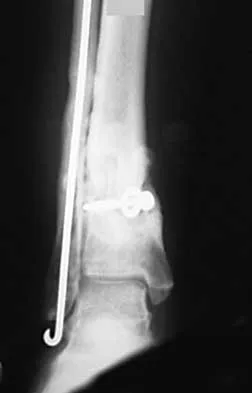

A 57-year-old woman with diabetes mellitus has purulent drainage from a lateral incision after undergoing open reduction and internal fixation of a displaced ankle fracture 10 days ago. Examination reveals moderate erythema and a foul odor coming from the wound. Cultures are obtained. What is the next most appropriate step in management?

Explanation

Early postoperative wound infections after open reduction and internal fixation should be treated with aggressive debridement and maintenance of stability of the fracture. If infection persists following healing of the fracture, the hardware should be removed. Carragee EJ, Csongradi JJ, Bleck EE: Early complications in the operative treatment of ankle fractures: Influence of delay before operation. J Bone Joint Surg Br 1991;73:79-82.